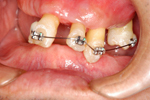

② 上の顎・歯周治療の後。矯正治療で歯の位置を修正

③ 上の顎・インプラント埋入の状態